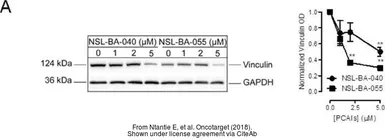

The data was published in the journal Oncotarget in 2018. PMID: 29899821

The data was published in the journal Oncotarget in 2018. PMID: 29899821

The data was published in the journal Oncotarget in 2018. PMID: 29899821

The data was published in the journal Oncotarget in 2018. PMID: 29899821

The data was published in the journal Oncotarget in 2018. PMID: 29899821

The data was published in the journal Oncotarget in 2018. PMID: 29899821

The data was published in the journal Oncotarget in 2018. PMID: 29899821